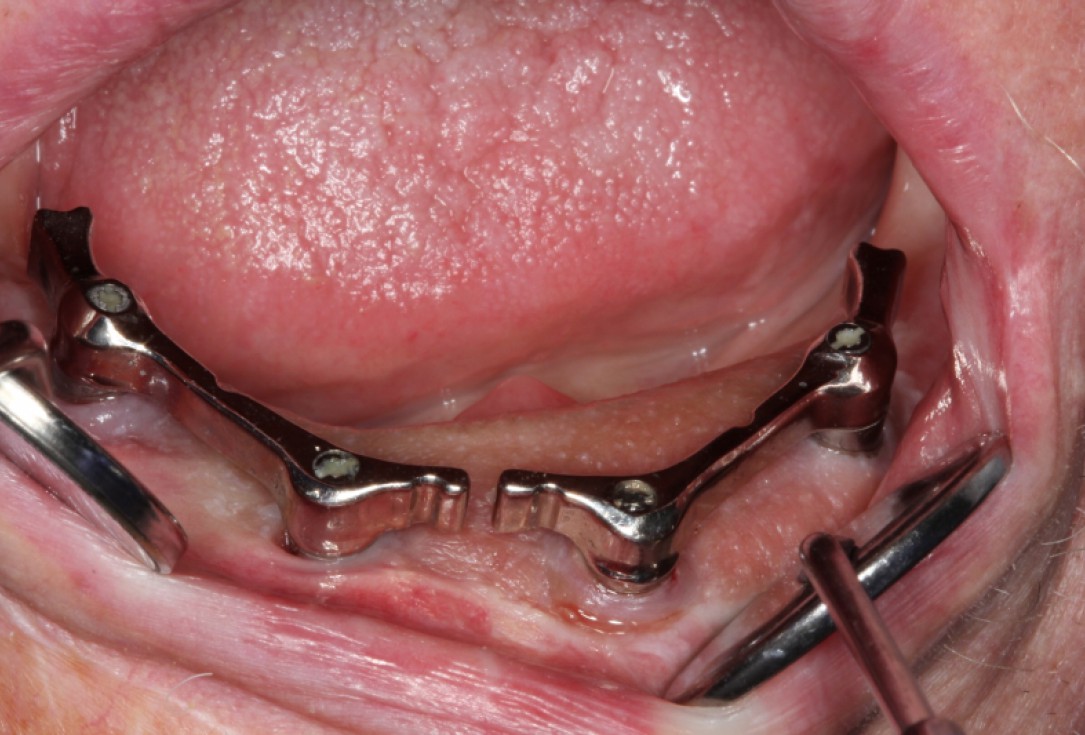

13/14 - Placement of bars for fixation of the prosthesis

Block augmentation with maxresorb®, collprotect® membrane & autologous bone blocks - Prof. Dr. Dr. D. Rothamel